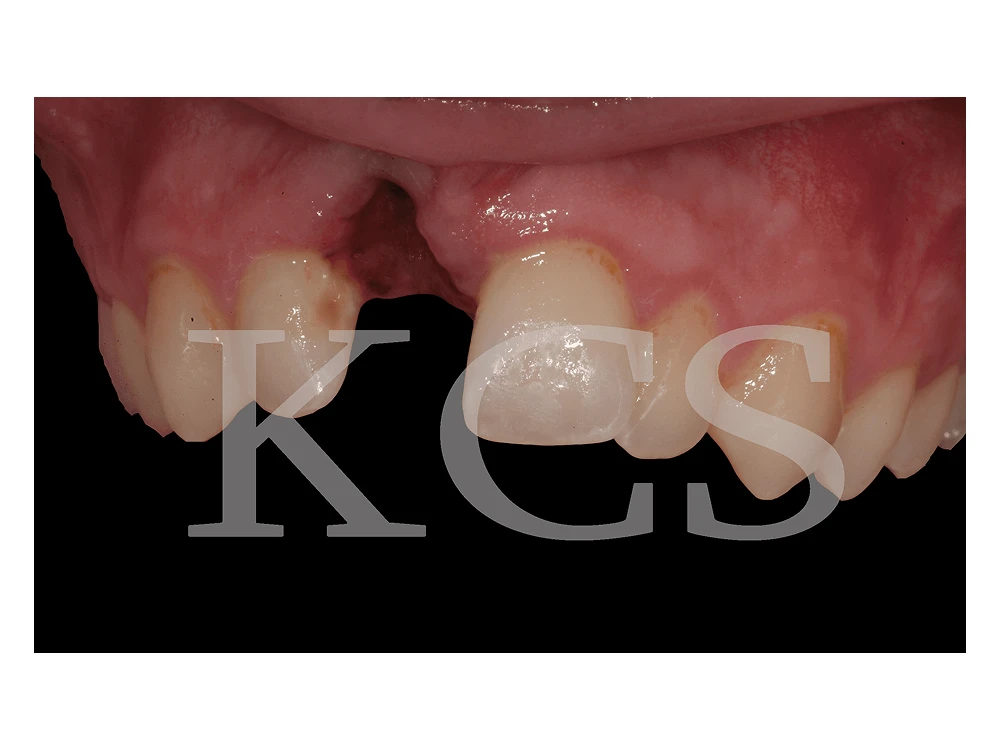

Patienten hade råkat ut för en olycka som drabbat höger framtand. Denna händelse resulterade i en långsamt permanent skada. I samarbete med den remitterande tandläkaren återställdes framtanden med hjälp av implantat.

Tanden avlägsnades.

Patientfall

Bild visar den färdiga tanden på plats.